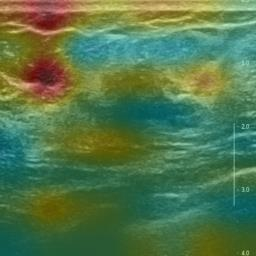

Ultrasonography is an important routine examination for breast cancer diagnosis, due to its non-invasive, radiation-free and low-cost properties. However, it is still not the first-line screening test for breast cancer due to its inherent limitations. It would be a tremendous success if we can precisely diagnose breast cancer by breast ultrasound images (BUS). Many learning-based computer-aided diagnostic methods have been proposed to achieve breast cancer diagnosis/lesion classification. However, most of them require a pre-define ROI and then classify the lesion inside the ROI. Conventional classification backbones, such as VGG16 and ResNet50, can achieve promising classification results with no ROI requirement. But these models lack interpretability, thus restricting their use in clinical practice. In this study, we propose a novel ROI-free model for breast cancer diagnosis in ultrasound images with interpretable feature representations. We leverage the anatomical prior knowledge that malignant and benign tumors have different spatial relationships between different tissue layers, and propose a HoVer-Transformer to formulate this prior knowledge. The proposed HoVer-Trans block extracts the inter- and intra-layer spatial information horizontally and vertically. We conduct and release an open dataset GDPH&GYFYY for breast cancer diagnosis in BUS. The proposed model is evaluated in three datasets by comparing with four CNN-based models and two vision transformer models via a five-fold cross validation. It achieves state-of-the-art classification performance with the best model interpretability.